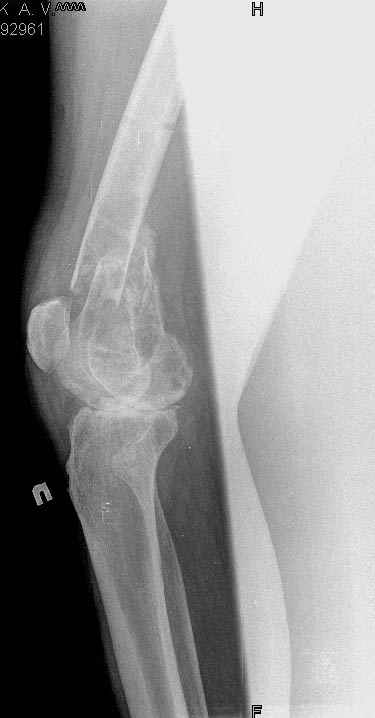

Коллеги!Окажите, пожалуйста, консультативную помощь.Мужчина, 41 год, 15 лет состоит на учете по поводу ревматоидного полиартрита, гормонзависимый (преднизолон получает нерегулярно). В процесс вовлечены крупные и мелкие суставы. 01.01.06 - без травмы наступил патологический перелом на границе н/3-с/3 бедра (перелом на фоне кистозных изменений?) Биопсия из зоны перелома - <реактивные изменения в очаге перелома>, без признаков опухоли. На рентгенограммах, помимо перелома, кистозные изменения на мыщелках б/берцовой кости и мыщелке бедра с другой стороны. До травмы со стороный коленных суставов был болевой синдром, функция практически в полном объеме. Какие будут предложения по тактика лечения перелома и кист на противоположом бедре? Заранее благодарю! С уважением, А.В.Владзимирский Донецкий НИИ травматологии и ортопедии Донецк, Украина